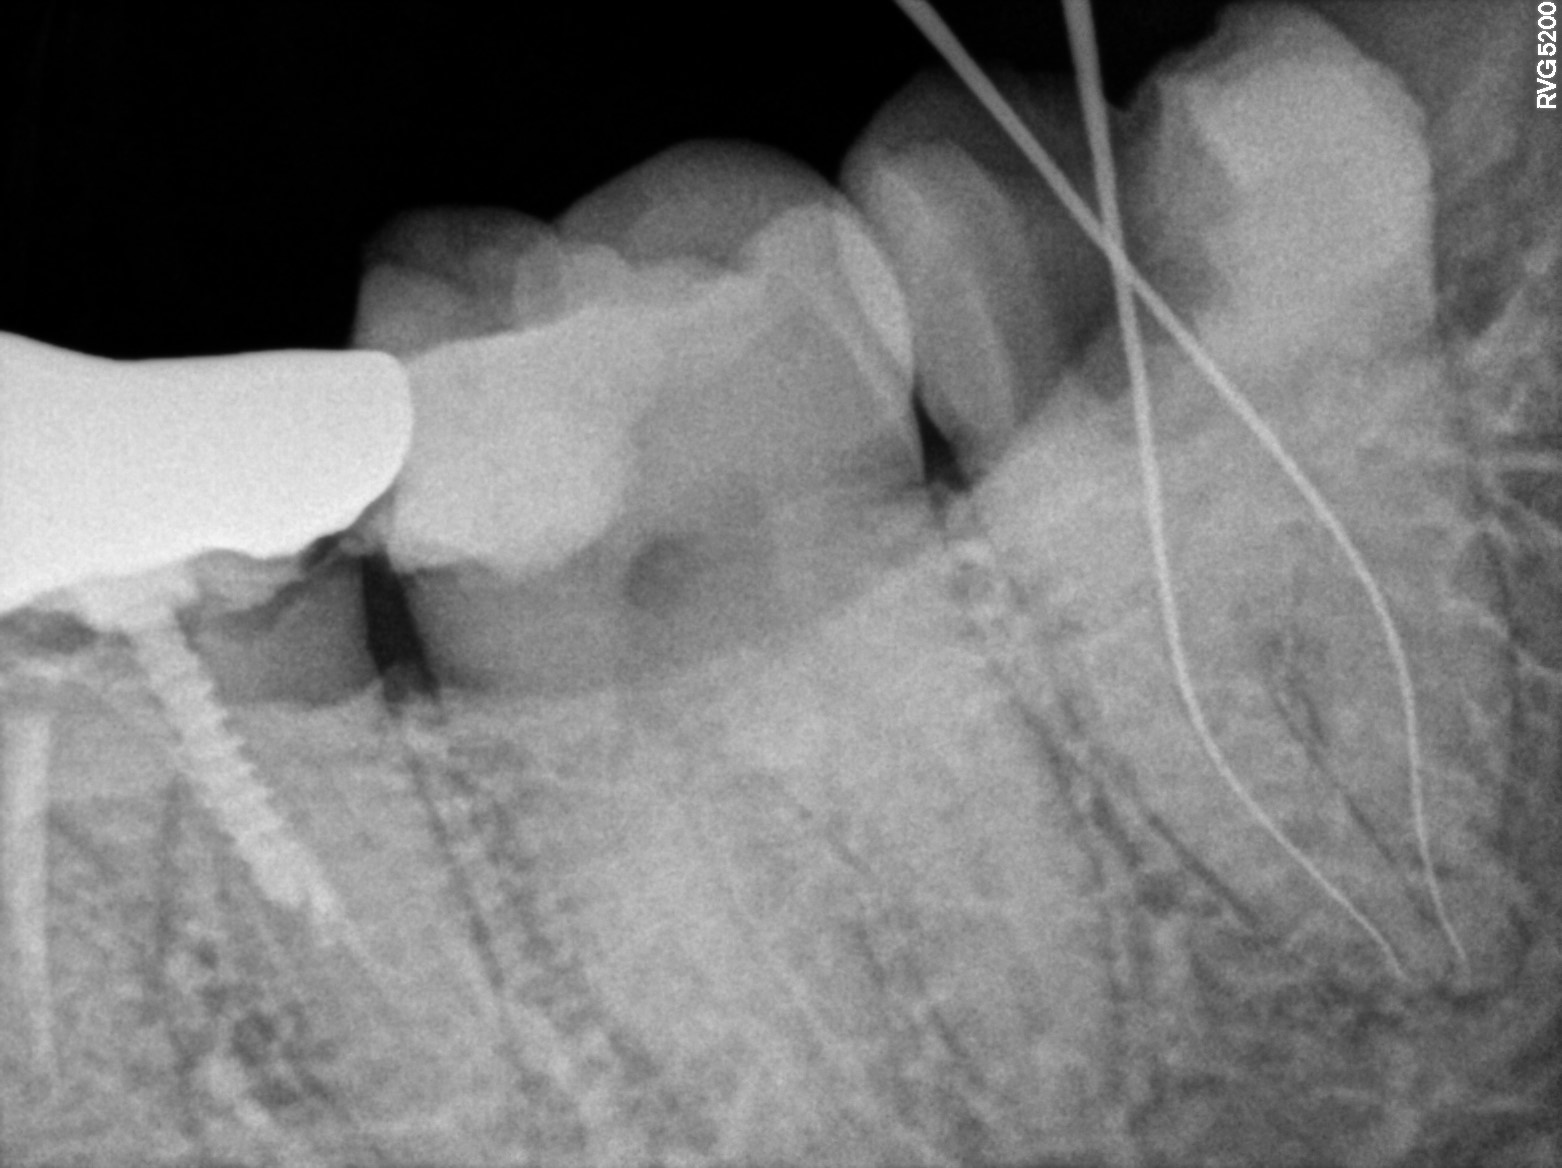

Dental Radiographs FHIR: DocumentReference · LOINC 24641-7

R58.jpg

24641-7